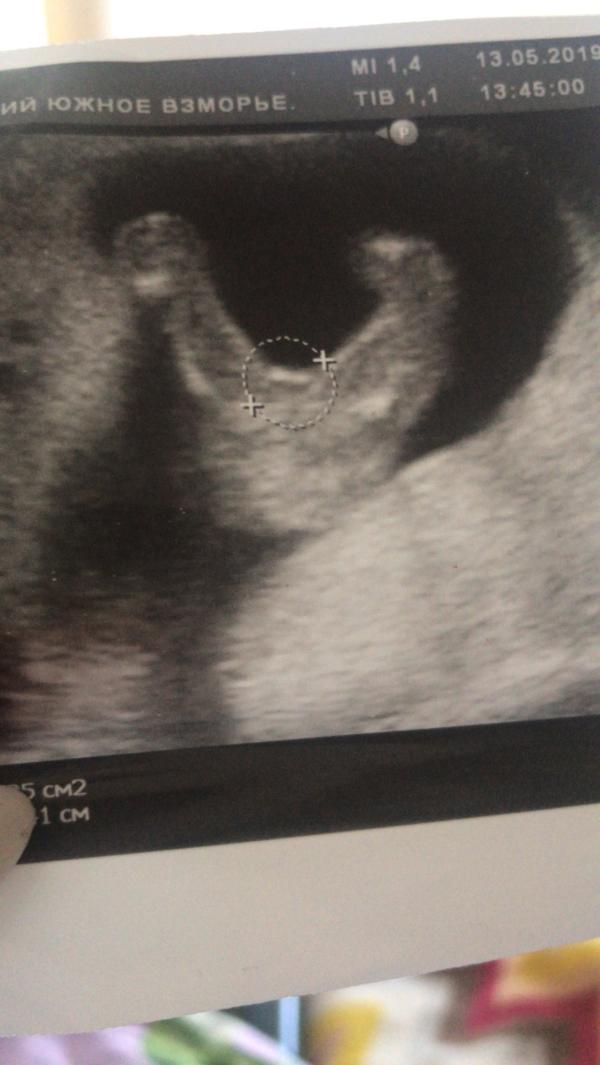

Сегодня были снова у Дмитрия Алеексеевича (Чепурняк) врач Узи в санатории «Южное взморье».

Дмитрий Алексеевич подтвердил нам пол, как и говорили на первом скрининге в перинатальном центре в Сочи, что будет девочка) и сейчас он сразу четко сказал) будет Пирожок и дал фотку Папе на память, чтобы напоминало😅где малышка раздвинув н...

Срок 16,2 ❤️